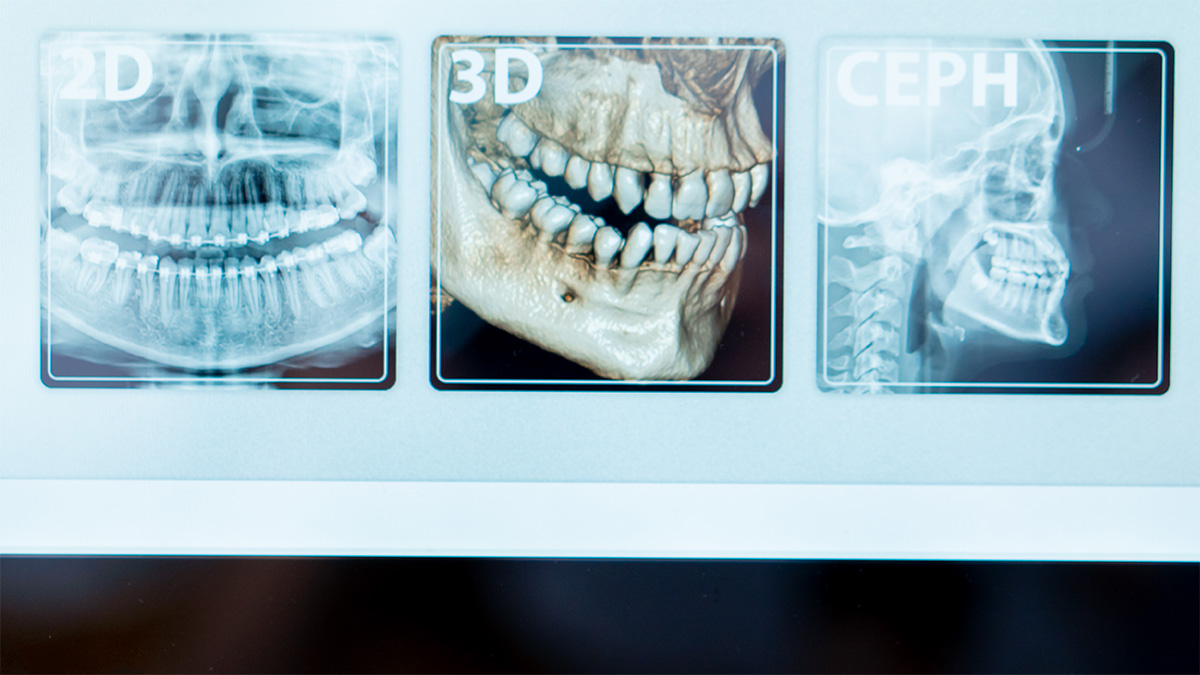

Uma radiografia 2D mostra uma projeção. É útil, rápida e, em muitos casos, suficiente. O problema é que a boca não é plana. Raízes, nervos, osso, seios maxilares e dentes inclusos existem em três dimensões, e o 2D pode sobrepor estruturas e esconder detalhes relevantes. A radiologia 3D, tipicamente através de CBCT, cria uma imagem volumétrica que permite avaliar espessuras ósseas, relações anatómicas e trajetos com muito mais precisão. Isto não significa que seja “melhor” por definição. Significa que responde a perguntas que o 2D não consegue responder com a mesma fiabilidade.

O ortopantomógrafo, por sua vez, é um exame panorâmico 2D que dá uma visão global de dentes e maxilares. É frequentemente a primeira fotografia de conjunto, útil para triagem e planeamento inicial. Quando a panorâmica levanta uma dúvida que pode mudar a decisão clínica, o 3D entra como ferramenta de precisão.